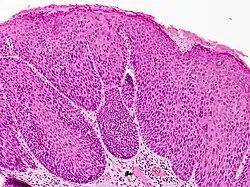

Bowenoid papulosis diagnosis requires a history, histologic examination, and clinical description of the condition.[9]